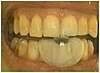

Usure des dents de la mâchoire inférieure par bruxisme.

Les dents du milieu ont perdu la moitié de leur hauteur initiale